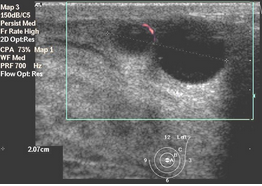

Выявление гиперэхогенного очага в полостной системе свидетельствует о конкременте (рис. ниже) или разрастании патологической ткани (рис. ниже) При наличии конкремента за ним определяется эхонегативная полоска – «дорожка», или «акустическая тень», которая отсутствует позади опухоли.

Сонограмма мочевого пузыря. В полости пузыря определяется гиперэхогенное образование – опухоль.